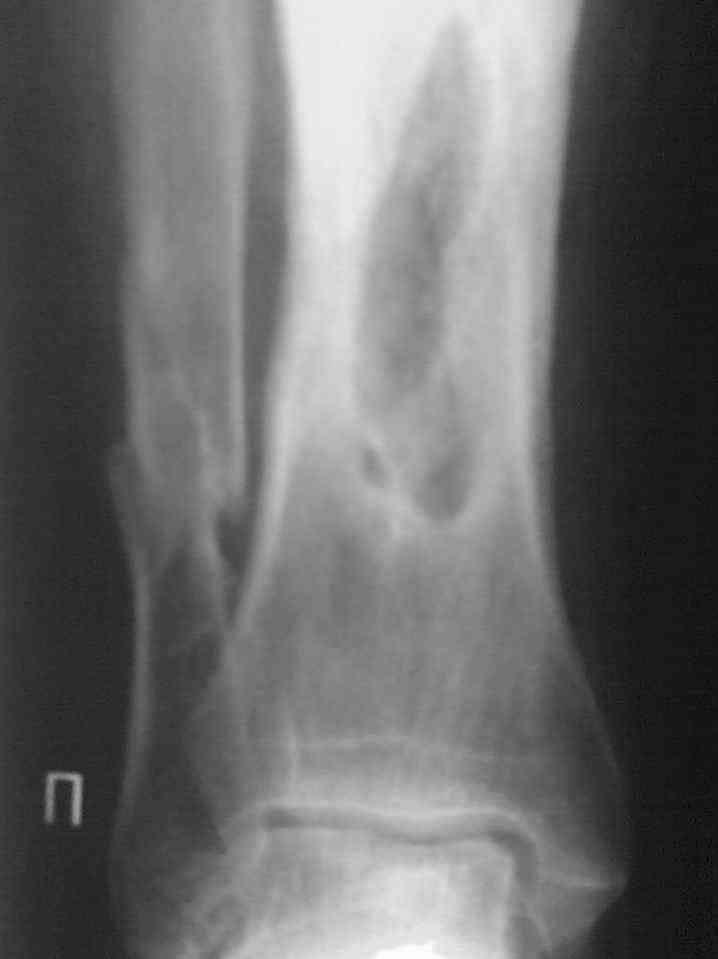

Здравствуйте коллеги! Прошу помочь с лечением больного. Мужчина в полном расцвете сил в апреле 2004 года получил травму - открытый оскольчатый перелом голени. Через 2 дня произведён МОС большеберцовой кости пластиной АО и винтами. Послеоперационный период осложнился остеомиелитом. Через 3.5 месяца пластина удалена. В марте 2005 года оперативное лечение в г. Екатеринбурге - санирование очага, некрэктомия. В июне 2006 года в ОКБ произведена секвестрэктомия, через неделю некрэктомия. Неоднократно получал антибактериальную терапию, в результате чего сформировалась сенсибилизация ко многим антибактериальным препаратам. В данный получает перевязки. Локально сохраняется кратерообразная гнойная рана, размерами до 4 х 3 см. Хотелось бы узнать Ваши мнения по поводу дальнейшего ведения данного пациента.

Да, конечно. Я ещё не до конца разобрался как посылатьсразу много снимков. Это последняя RG - грамма.

Фото(038)а.jpg

Выкладываю снимки в хронологическом порядке. Снмки все какие есть у больного.